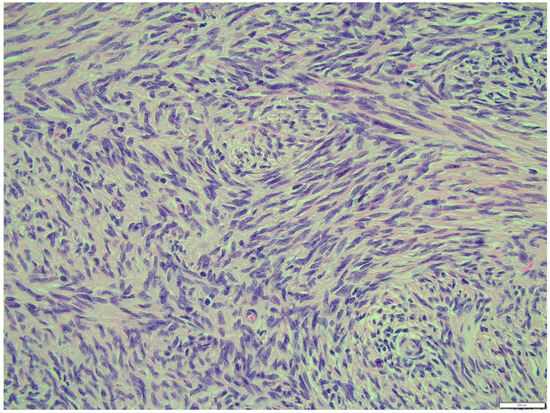

The fibroma was composed of uniform medium-sized, spindle-shaped cells with indistinct borders and a regularly shaped and sized oval, dark or gray nucleus to long thin nucleus cells. The indistinct nucleoli and finely stippled chromatin in the nucleus were observed. The nucleus/cytoplasm ratio favored the cytoplasm. The cytoplasm was pink and long, as is common in mature spindle cells. Spindle cell anisocytosis and anisokaryosis were mild to moderate (Figure 14). Mitoses were typical. The rate of mitoses was low—2 per 10 fields at 400 magnification. The spindle-like cells were arranged in sweeping fascicles angled in a chevron-like or herringbone pattern (Figure 15). In addition, storiform areas were observed (Figure 16). The stroma had a delicate intercellular network of collagen, but a few areas of “keloid-like” sclerosis/hyalinization were found (Figure 17). The histological pattern is typical for fibrosarcoma, but not for fibroma. However, tumor cells lacked marked atypia. The ovary-derived fibroma was considered to be a pure stromal tumor of the ovary.

Figure 16. Storiform areas, fibroma part. HE, 200× magnification.